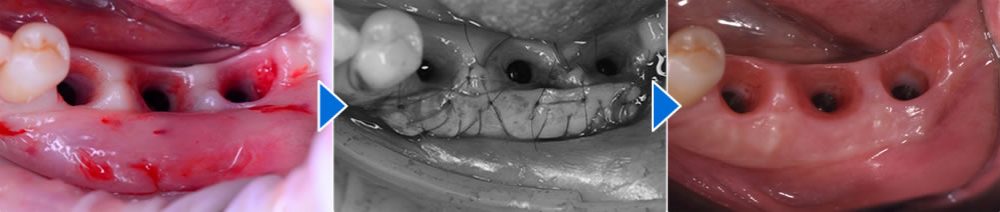

FGG(遊離歯肉移植術)の実施

インプラントと顎の骨がしっかり結合した後、インプラント周囲の歯肉を保護し、清掃性やメンテナンス性を高めるためにFGG(遊離歯肉移植術)を行いました。この処置により、長期的に安定したインプラント周囲環境を維持しやすくなります。